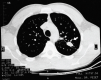

Fig. 1. Varón de 19 años diagnosticado de tuberculosis activa en el cultivo del broncoaspirado. Entre los hallazgos de la tomografía computarizada de alta resolución (HRCT) destaca la presencia de macronódulos (flecha).